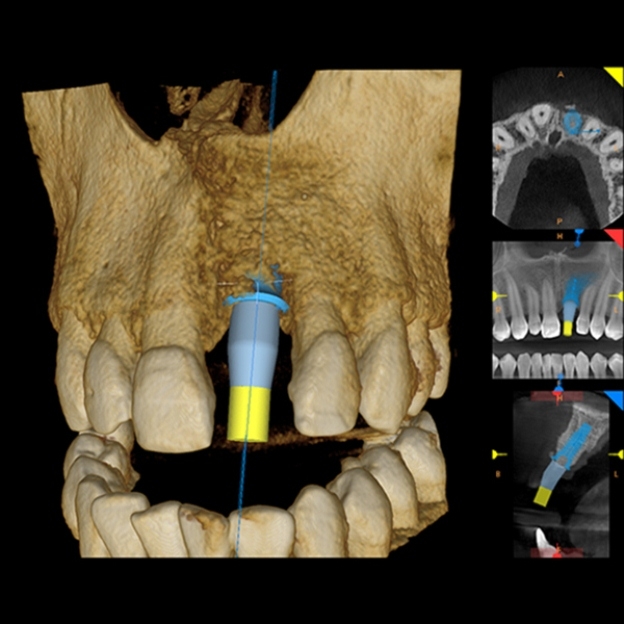

– przed leczeniem implantologicznym – skan 3D umożliwia ocenę ilości, objętości i jakości kości u pacjenta, potrzebnej do wszczepienia implantu zębowego. Na jego podstawie czas zabiegu chirurgicznego zostaje skrócony, a ryzyko powikłań znacząco zmniejszone,

- Tomografia zębów 3D – tomografia komputerowa 3D zębów jest niezbędna :

-w kierunku diagnostyki chorób zatok szczękowych oraz stanu kości szczęk i żuchwy co jest wykorzystane przez periodontologa lub chirurga do dalszych zabiegów

–w diagnostyce trudnych przypadków leczenia kanałowego (endodontycznego) – np. w celu lokalizacji złamanego narzędzia lub odnalezienia dodatkowego kanału w korzeniu zęba itp. ( wykonywana jest wówczas mikrotomografia CBCT). Badania tomografii komputerowej wykonywane są za pomocą nowoczesnego tomografu